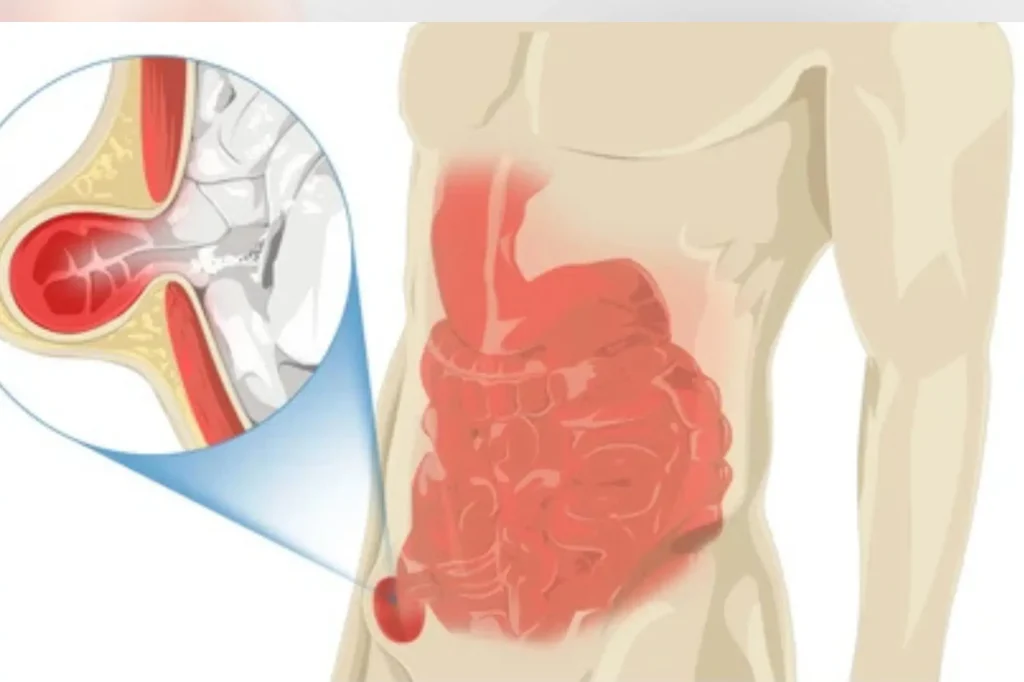

Bilateral Inguinal Hernia

A laparoscopic solution for a common yet uncomfortable issue, Inguinal Hernia surgery helps you return to your routine with minimal downtime and scars.

An inguinal hernia occurs when a portion of tissue, such as the intestine, pushes through a weak spot in the abdominal muscles near the groin. It may result in a visible bulge and discomfort, especially while lifting, bending, or coughing. Laparoscopic inguinal hernia repair is a minimally invasive method to correct this condition with fewer complications and a quicker recovery than open surgery.

- Groin swelling or bulge

- Pain during physical activity

- Numbness or heaviness in the groin

- Digestive discomfort or constipation

- Hernia recurrence after prior surgery

- Laparoscopic hernia repair (TAPP or TEP technique)

- Mesh placement to reinforce the wall